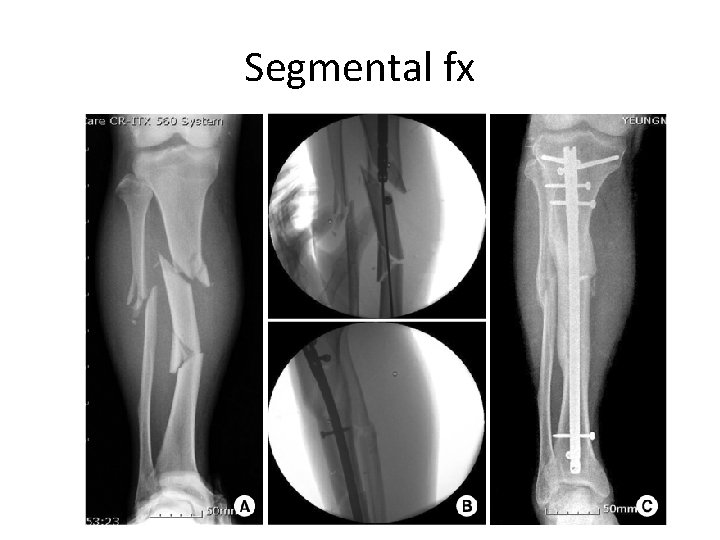

Fractures • Simple ; spiral, oblique and transverse • Complex – Complete separation of bone; major blow, intraarticular , comminution and segmental • Open vs close

Segmental fx